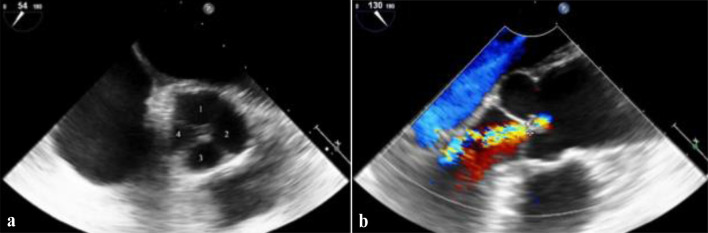

四尖瓣主动脉瓣(QAV)是一种罕见的先天性异常,根据尸检和超声心动图研究估计发病率为0.008%至0.043%。虽然通常无症状,但它可导致进行性主动脉反流(AR),左心室(LV)功能障碍和心律失常,如心房颤动(AF)。由于其罕见性,QAV经常被误诊或偶然发现,强调了对出现不明原因心力衰竭症状和心律失常的年轻患者进行先进心脏成像的必要性。我们报告一例41岁女性患者,因新发呼吸困难入院,纽约心脏协会(NYHA)分类为III级,欧洲心律协会(EHRA)症状分类为2b级的持续性房颤引起心悸。没有先天性或结构性心脏病的家族史,动脉高血压是唯一确定的易感条件。最初的经胸超声心动图显示中度AR,但在肺静脉隔离前进行的更详细的经食管超声心动图偶然发现QAV。进一步的心脏磁共振成像证实主动脉根部尺寸正常,早期左室重构。对患者进行保守治疗,控制心率,抗凝,并定期随访以监测疾病进展。本病例强调了先进的成像技术在诊断以不明原因心衰症状和心律失常为表现的罕见结构性心脏异常的年轻患者中的重要性。QAV的早期识别允许及时的医疗干预,最佳的患者监测和预防长期并发症。定期随访对于监测疾病进展和确定是否需要手术干预至关重要。